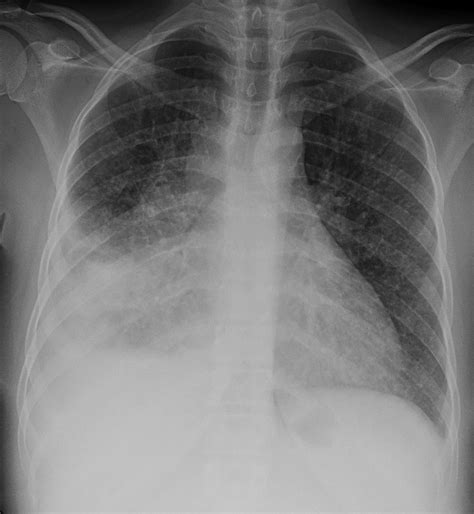

In the realm of medical diagnostics, the Tb X Ray has long been a cornerstone tool for detecting and monitoring tuberculosis (TB). This imaging technique provides invaluable insights into the lungs and other affected areas, aiding healthcare professionals in diagnosing and treating this infectious disease. Understanding the significance, process, and advancements in Tb X Ray technology is crucial for both medical practitioners and patients alike.

Tuberculosis is a bacterial infection caused by Mycobacterium tuberculosis, primarily affecting the lungs but also capable of spreading to other parts of the body. Symptoms can include persistent cough, chest pain, and weight loss. Early detection is key to effective treatment and prevention of spread. The Tb X Ray is a non-invasive method that uses electromagnetic radiation to produce images of the internal structures of the body, particularly the lungs.

It’s important to note that while Tb X Ray can provide valuable information, it is not always conclusive. Additional tests, such as sputum tests or CT scans, may be required for a definitive diagnosis.